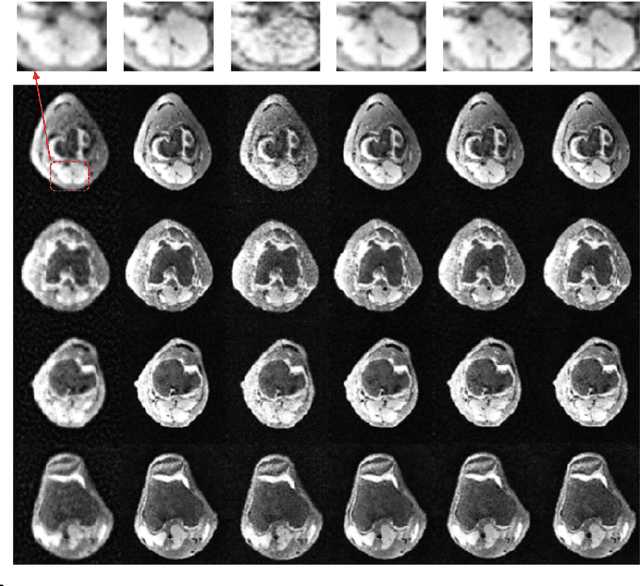

Recovering high-quality images from limited sensory data is a challenging computer vision problem that has received significant attention in recent years. In particular, solutions based on deep learning, ranging from autoencoders to generative models, have been especially effective. However, comparatively little work has centered on the robustness of such reconstructions in terms of the generation of realistic image artifacts (known as hallucinations) and quantifying uncertainty. In this work, we develop experimental methods to address these concerns, utilizing a variational autoencoder-based generative adversarial network (VAE-GAN) as a probabilistic image recovery algorithm. We evaluate the model's output distribution statistically by exploring the variance, bias, and error associated with generated reconstructions. Furthermore, we perform eigen analysis by examining the Jacobians of outputs with respect to the aliased inputs to more accurately determine which input components can be responsible for deteriorated output quality. Experiments were carried out using a dataset of Knee MRI images, and our results indicate factors such as sampling rate, acquisition model, and loss function impact the model's robustness. We also conclude that a wise choice of hyperparameters can lead to the robust recovery of MRI images.